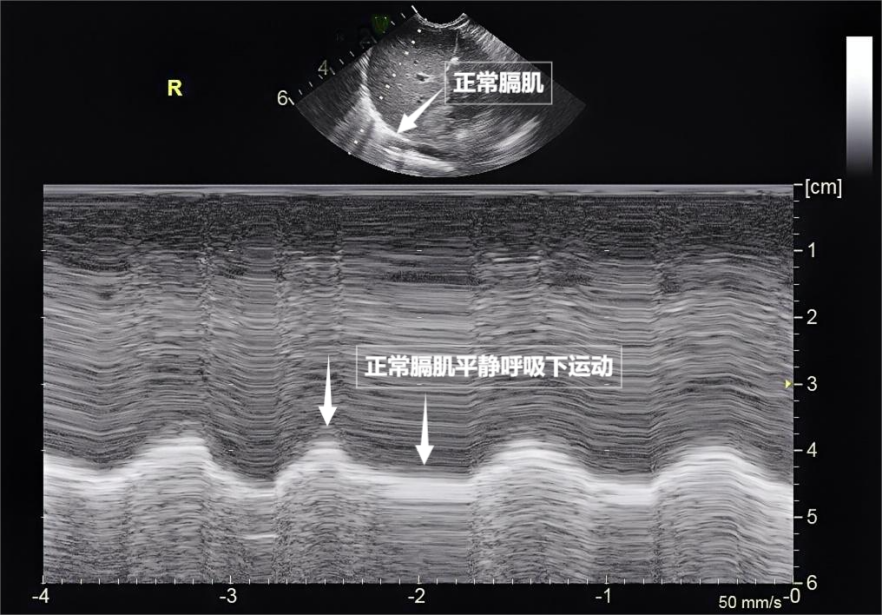

图为正常膈肌超声表现

需要强调的是,随呼吸规律上下移动(见下图)。

超声波会加重肺部疾病吗